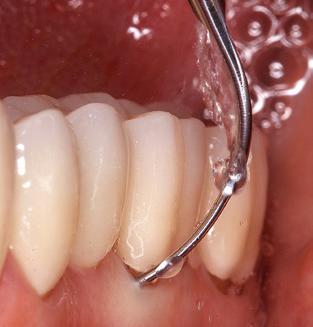

The current working concept for SPT

Fig. 4: Flexible probes with millimetre markings are recommended for the probing of dental implants (e.g. Colorvue Kit PCV11KIT6, Hu­Friedy). – Fig. 5a and b: A straight working tip (1P, W&H Dentalwerk Bürmoos GmbH) is a suitable instrument for use on all natural teeth. – Fig. 6: Curved working tips (3Pr/3Pl, W&H Dentalwerk Bürmoos GmbH) lend themselves to the processing of difficult-to-reach areas of the tooth and root surfaces (e.g. furcations). – Fig. 7: The tapered, hexagonal implant cleaning tip (1I, W&H Dentalwerk Bürmoos GmbH) permits atraumatic and efficient cleaning of the crown and abutment surfaces. – Fig. 8: Titanium and carbon curettes are suitable instruments for the manual cleaning of the implant surfaces.

Of course, the use of instruments for mechanical removal of the biofilm is a central component of SPT and thus of primary significance. Consequently, the SPT workflow comprises both supragingival and subgingival cleaning. In our concept, a combination of hand instruments and machine cleaning has proven advantageous. A number of options are available for the mechanical procedures: sonic devices, ultrasonic devices and powder jet devices.

Good illumination of the working field facilitates the process considerably. The system used by the authors achieves this thanks to a 5x LED ring integrated in the handpiece. Naturally, a range of working tips for different indications is also offered. A straight, universally employable tip is the basic instrument required for machine cleaning of natural teeth (Fig. 5a and b). Curved tips, which allow access to exposed furcations, are also available for hard-to-reach areas in the posterior region (Fig. 6).